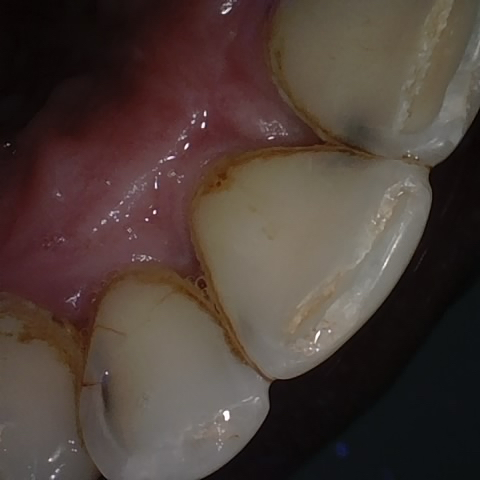

Annotated as "Good"